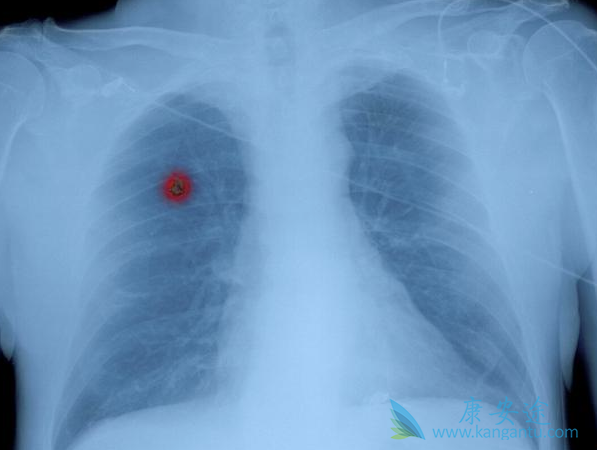

晚期肺癌治疗后存活10年以上早就不是梦

晚期肺癌治疗

在医生眼里,肺癌分4期,1(I)、2(II)、3(III)、4(IV)期,每一期又分a和b,比如1a和1b期,1a期是最早期的肺癌,1b也属早期,但比1a期相对来说稍晚。在我们老百姓眼里,癌症怎么都得分个早中晚期,虽然这种分法不甚科学,但是长此以往医生也顺应了这种说法,一般来说,1期肺癌属于早期。2a期属于中期偏早,2b和部分可手术的3a期属于中期,另外一部分无法手术根治的3a期则属于中期偏晚。3b期和4期肺癌归结为晚期肺癌。什么样的肺癌才属晚期?肺癌,顾名思义长在肺上,那么如果肺脏以外的器官出现了转移(metastasis,M),可以直接定义为晚期,比如骨转移,脑转移,肾上腺转移,肝转移等,如果出现了多器官多部位的转移,那么就是晚期中的晚期了。

其实吧,晚期肺癌最容易出现转移的部位是肺脏本身,如果肺脏本身出现了多发的转移结节,尤其是右侧肺癌出现了左肺转移或者左肺癌出现了右肺转移,这也是晚期肺癌。再来说淋巴结转移,肺癌出现了淋巴转移可不一定属于晚期,或者可以这么说,不管淋巴结转移的有多么厉害,都不属于4期,最多是3B期肺癌。淋巴结转移根据部位的不同,2a、2b、3a、3b期肺癌都可能会伴有淋巴结的转移,只不过淋巴结转移的部位不同而已,离原发病灶越远的淋巴出现转移,则提示分期越晚。3b期和4期肺癌因为往往无法获得根治,注意这里我的用词是往往,仍然有很少部分的晚期肺癌经过积极治疗是可以根治的。而我这里要提的是那些无法获得根治的晚期肺癌,那么我们的治疗目标就是尽可能延长患者的生命,并保证一定的生活质量。晚期肺癌治疗后可以存活10年以上,早就不是梦了。